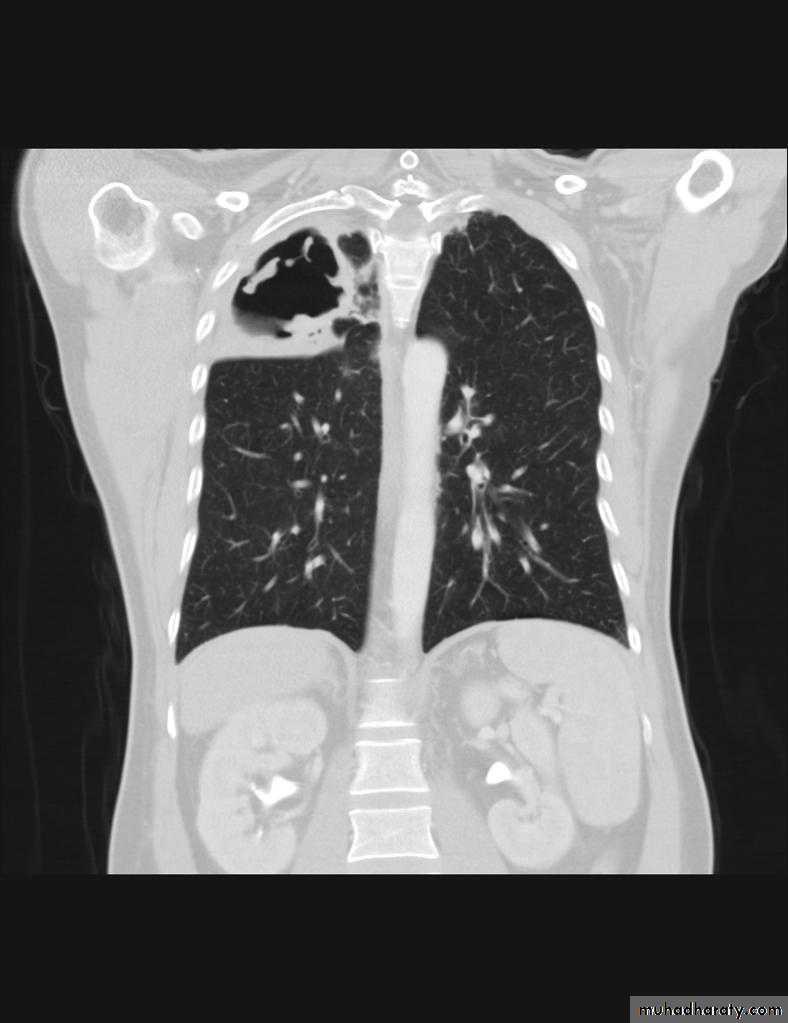

RT UL Consolidation